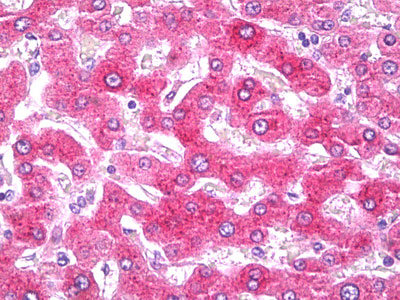

Anti-CRP antibody IHC of human liver. |